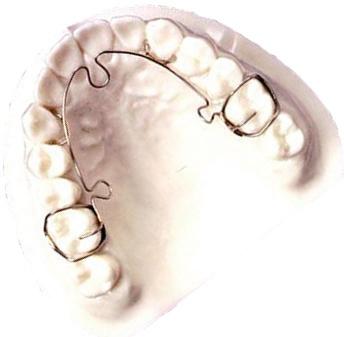

A very fun and very special advancement when it comes to doing braces to finish up a TMJ patient is the digital impression system. This system basically uses a camera to videotape the teeth and the computer effectively “stitches” all the videos together to show the lab what the teeth look like. In addition, the digital impressions are the most accurate way to see the teeth and jaw bones. Then, the braces manufacturer

Why TMJ Technology Is So Important

uses a device to “cut’ each bracket to the best fit possible for every individual tooth. This means that each bracket is custom made, by hand (the hand of a computer guided laser that is) to the proper tip and torque needed to achieve the best result in the shortest time possible. Think of it like GPS for your trip up to Canada

the computer will design the least difficult, quickest, and most efficient path to get you there.

ALF ( Advanced Light Force

ALF Therapy has proven to be an extremely valuable tool for those patients who have:

• A need for facial guidance

• Palate expansion

• Narrow palates

• Breathing issues

• TMJ dysfunction

• Craniofacial pain

• Crowded/crooked teeth

• An avoidance for extractions

• Crossbite, overbite or underbite

• Cranial asymmetry

• Sleeping problems — snoring

• Recommendations for jaw surgery

Our ALF appliances are certified by Dr. Darick Nordstrom. He has personally instructed our ALF-certified technicians on the proper design and fabrication techniques to ensure that each technician is capable of creating authentic ALF appliances worthy of certification. The seal below is his stamp of approval.

Dr. Brown is highly trained in ALF (Advanced Light Force) therapy. He has over 500 hours in ALF therapy training and has lectured around the world teaching ALF techniques with Dr. Nordstrom, the creator of the ALF appliances. The ALF appliances are thin, conservative appliances that can be used on the upper and lower arches. They hide behind the teeth, are removable and are basically invisible when being worn. This innovative treatment approach is used to address neurological, orthodontic and orthopedic issues, and the benefits are vast. Each appliance is unique to the patient and designed by the doctor to achieve specific goals relating to health, beauty and function. No ALF appliance is the same, and treatment is pain-free.